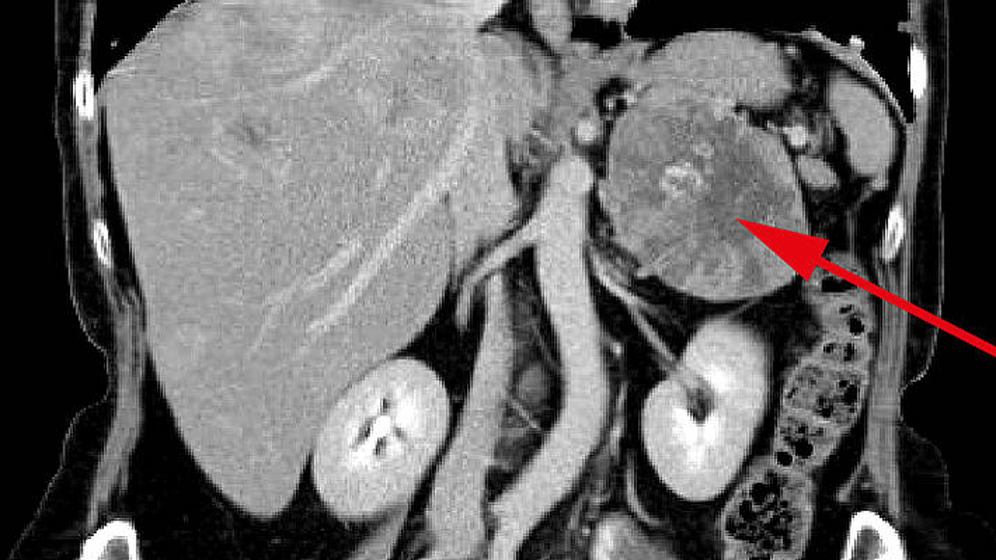

Nebennierentumoren gehören laut Deutscher Gesellschaft für Endokrinologie zu den häufigsten Tumoren beim Menschen überhaupt. Drei Prozent der über 50-Jährigen haben Nebennierentumore. Bei den über 80-Jährigen ist sogar jeder zehnte betroffen. 80 bis 90 Prozent dieser Tumore, die meist zufällig, zum Beispiel bei einer Computertomografie bei Gallenproblemen, Nierensteinen oder Rückenleiden, entdeckt werden, sind jedoch gutartig und vermeintlich harmlos. Vermeintlich deshalb, weil eine leicht gesteigerte Produktion des Hormons Kortisol, die viele dieser Tumore mit sich bringen, vor einiger Zeit die Meinungen spaltete: Muss man den Tumor operativ entfernen oder nicht?